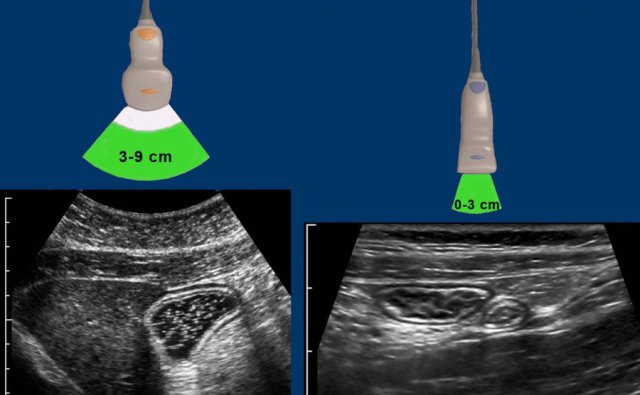

For the average abdominal US program with patients of varying habitus, still three probes is the minimum.

The cm’s indicate the range where image resolution is optimal.

Since bowel lies close to the abdominal wall, the middle and small probe are the workhorses in US of the GI tract.

Choice of the probe is based on the depth where the bowel is visualized during compression.

For example, the fluid-filled stomach in this obese patient (left), is best studied with the middle-transducer, the normal ileum and appendix in a thin patient (right), with the small transducer.